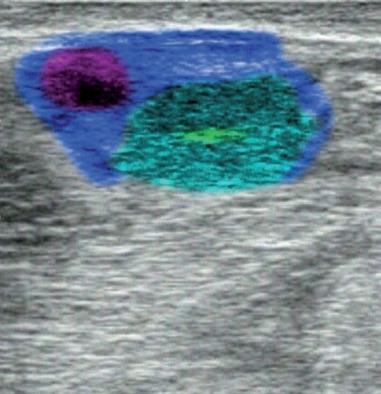

La exploración ecográfica de los ovarios nos permite diferenciar fácilmente las estructuras fisiológicas presentes. Así veremos que los folículos aparecen en la imagen como estructuras más o menos circulares y negras, que no suelen hacer prominencia en la superficie del ovario. Por contra, las estructuras luteínicas presentarán una imagen de un tono gris oscuro, con una forma circular y en la mayor parte de los casos apreciaremos una cabeza, más o menos evidente, que hace una prominencia en la superficie ovárica. En el interior de esta estructura luteínica puede verse una pequeña cavidad con líquido (anecogénica) o bien una especie de banda blanca (hiperecogénica) que atraviesa el cuerpo lúteo de un lado a otro (travécula).

Muchos cuerpos lúteos en los 2-3 primeros días después de la ovulación pueden presentar una imagen ecográfica similar a las que se muestran a continuación. La parte central es hiperecogénica y se corresponde con el coágulo en proceso de transformación, tal como se puede ver en la primera imagen de la serie.

Ovario

Cuerpo Lúteo

Cavidad del Cuerpo Lúteo

Folículo

Travécula del Cuerpo Lúteo

Coágulo del Cuerpo Lúteo Joven